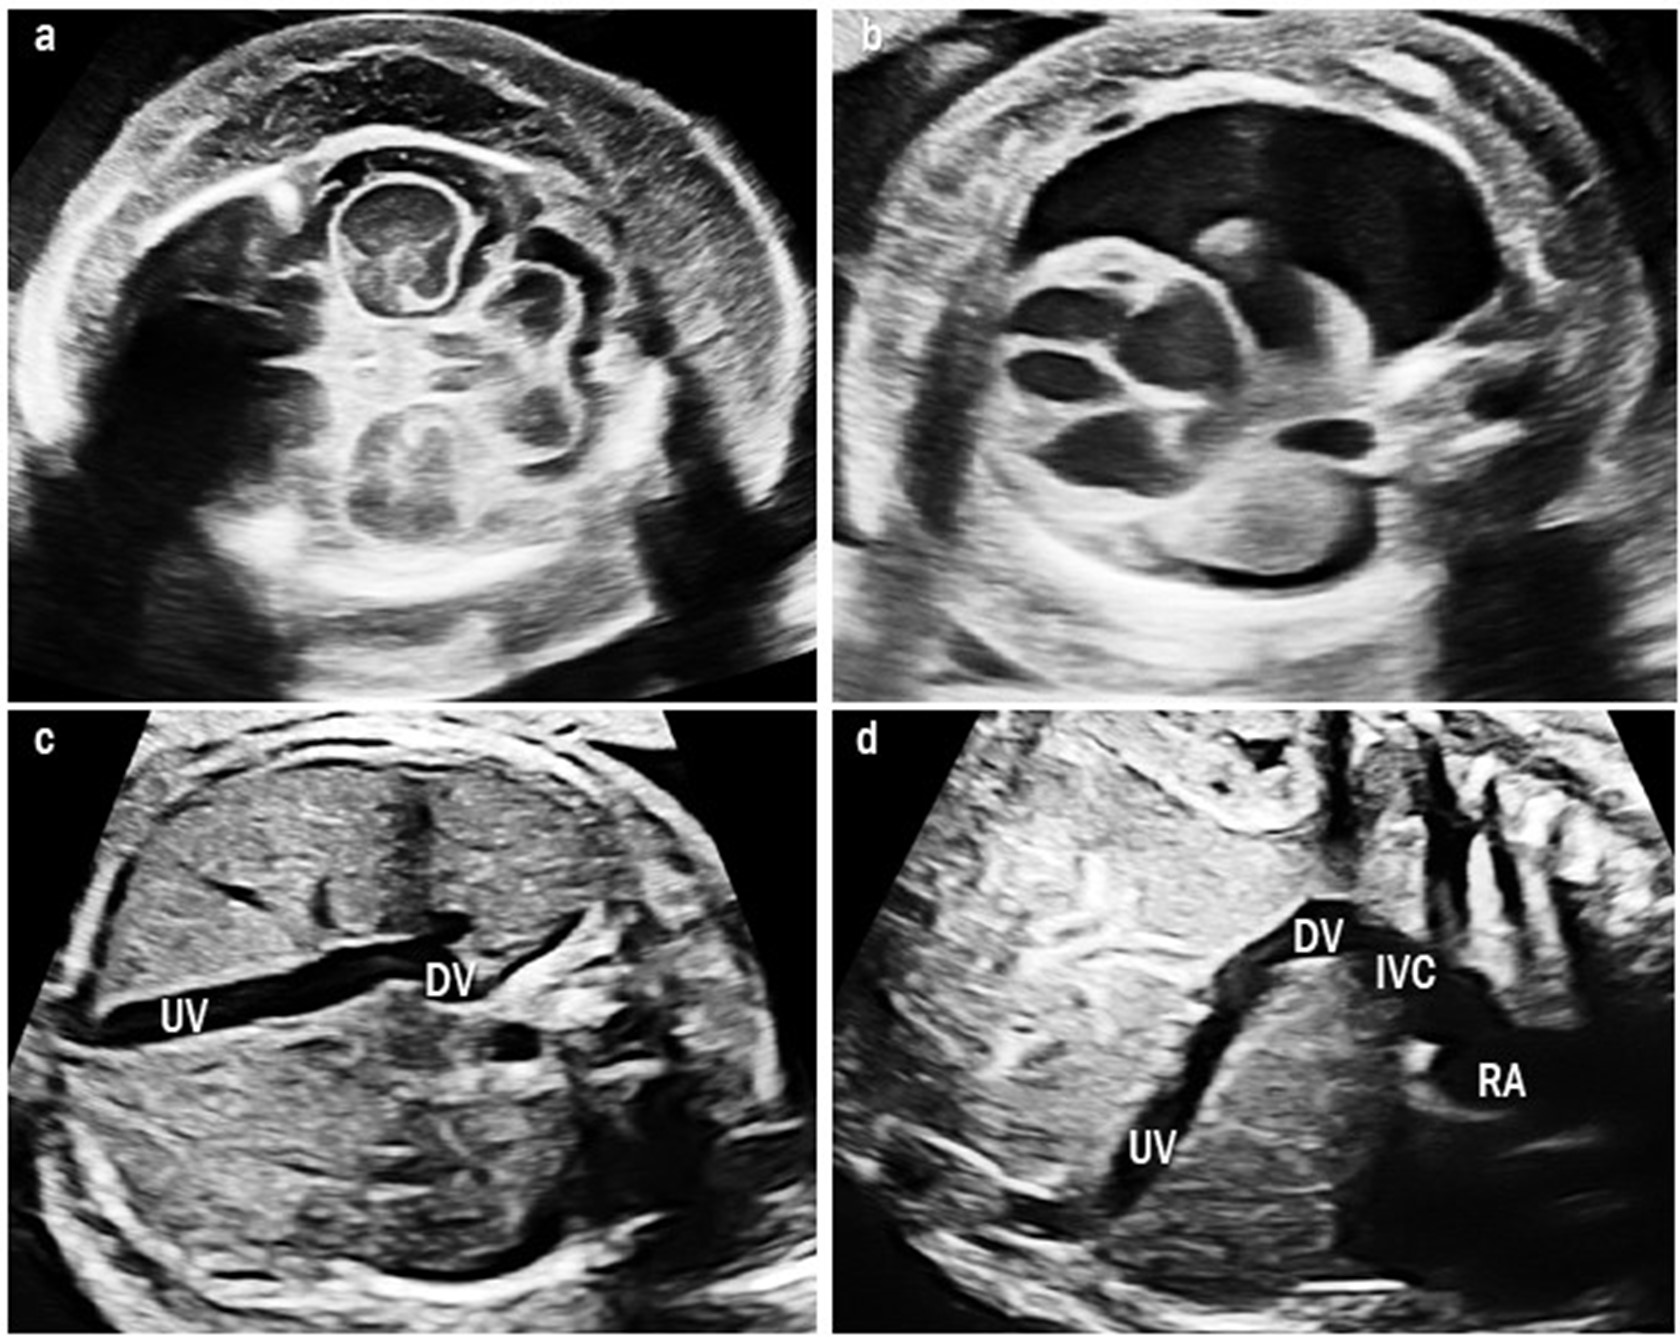

We found one case of type II UPSVS (case 9). The fetus had a short DV that drained into the IVC, but other structures of the umbilical-portal-DV complex were intact. The fetus showed cardiomegaly and fetal hydrops with severe skin edema and pleural effusion (Fig. 3). This fetus was confirmed to have a 3p deletion. The fetal hydrops resolved after birth. At the time of writing, the patient was 17 months old and had developmental delay.

Fig. 3.Ultrasound images of type II umbilical-portal-systemic venous shunt in case 9. The fetus showed severe fetal hydrops: (a) severe skin edema and (b) pleural effusion. (c) Transverse abdominal image shows the UV connected to the DV and it drains at the lower site than usual. (d) Sagittal image shows a short DV draining into the IVC below the diaphragm. UV, umbilical vein; DV, ductus venosus; IVC, inferior vena cava; RA, right atrium.